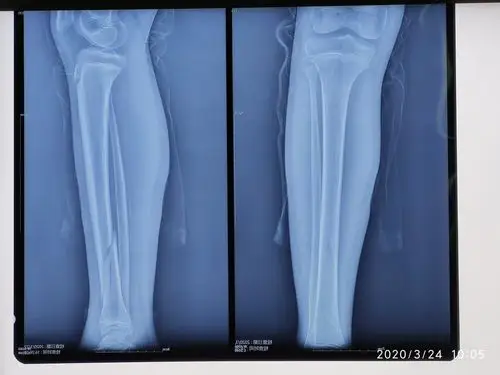

儿童胫骨远端干骺端骨折的微创手术治疗 - 好大夫在线